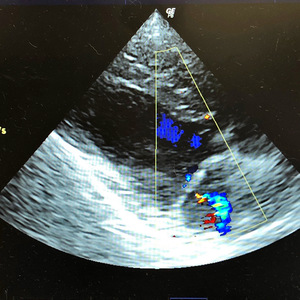

動物別症例集 : 犬 4ページ目 指の扁平上皮癌 犬の前十字靭帯断裂 犬の潜在精巣 犬の肛門周囲腺腫・肛門周囲腺癌 犬のマイボーム腺腫 犬の耳血腫 犬の断尾(日本テリア) 犬の僧帽弁閉鎖不全(MMVD) 犬の橈尺骨骨折 犬の椎間板ヘルニア <<前のページへ|1|2|3|4|5|次のページへ>>